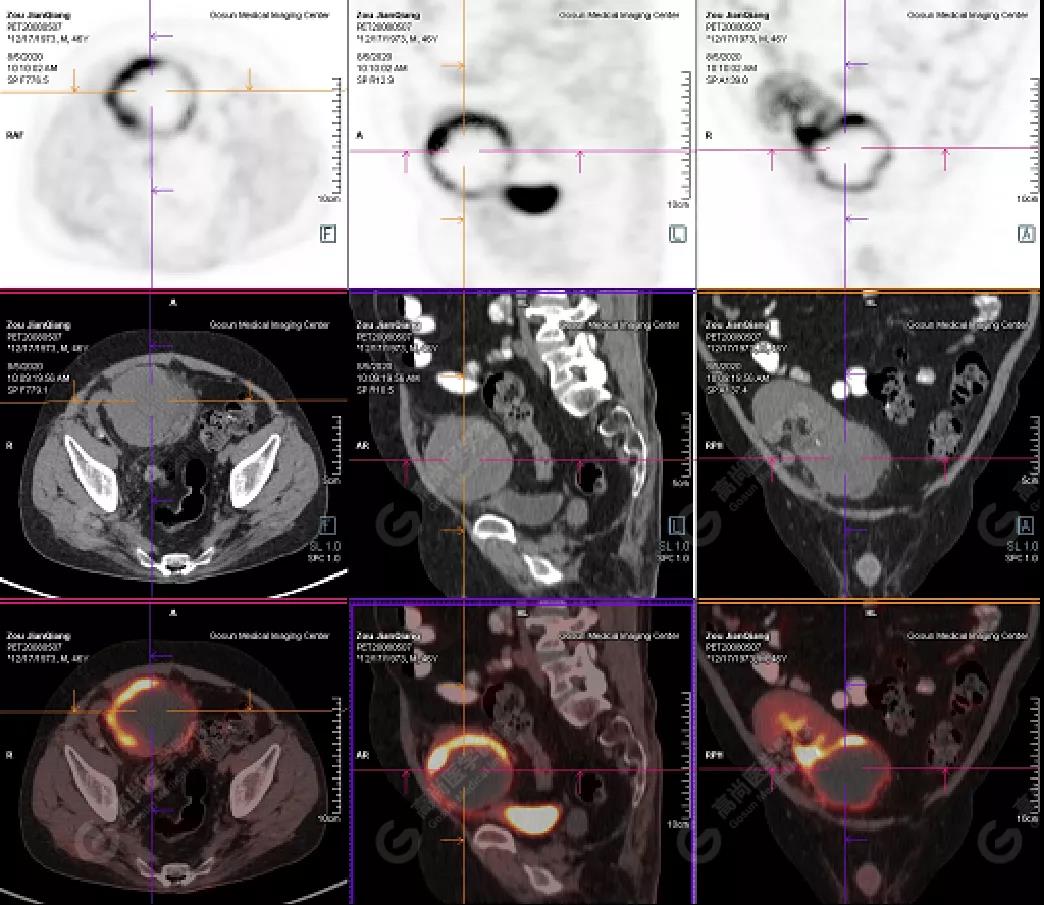

PET/CT檢查

↑移植腎下部等密度腫塊,代謝環(huán)狀增高,SUVmax13.4,中心代謝缺損

移植腎腫物穿刺活檢病理:移植后EBV陽性的彌漫大B細(xì)胞淋巴瘤。